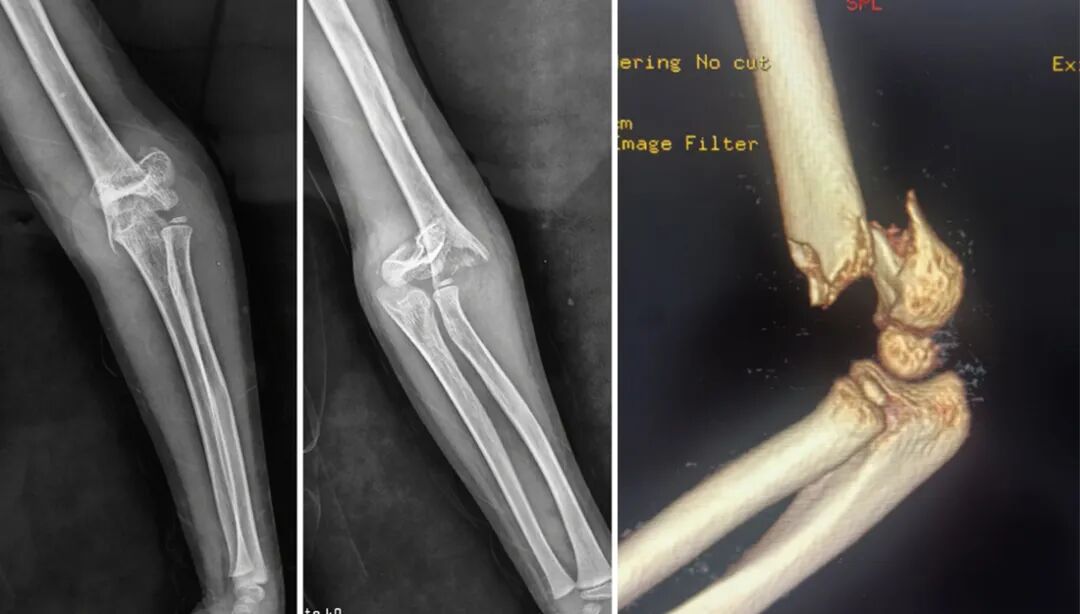

术前

术后

万般无助之时,他们来到我院,刘友饶主任接诊后详细了解患儿伤情,考虑骨折错位严重,已经压迫肘部神经血管,不紧急手术存在很大的骨筋膜室综合征风险,也深切体会到家属的焦急,他没有丝毫犹豫,果断决定为孩子安排急诊手术。为抢抓救治时间,尽早缓解患儿痛苦,医护团队放弃周末和下班休息时间,在深夜11点赶到医院,迅速投入到紧张的术前准备工作,制定手术方案。凌晨2点,顺利通过闭合复位经皮克氏针固定,以“零切开”方式高效完成了手术治疗。术后,患儿状况良好,复查骨折得到良好复位,目前正在积极康复中。